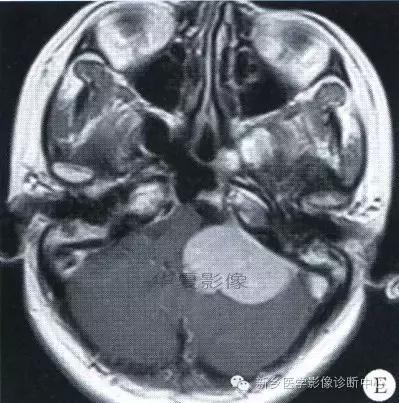

中枢神经系统内原发性黑色素瘤少见, 因脑和脊髓的软脑( 脊) 膜及蛛网膜上含有黑色素细胞, 黑色素可发生于软脑( 脊) 膜的任何部位,故其发生部位常位于脑( 脊髓) 表面, 沿软脑膜生长; 而继发性黑色素瘤同一般转移性肿瘤, 常位于灰白质交界区。

影像表现:常表现为短 T1 高信号, 短T2WI 低信号,又因为黑色素瘤是富血管性肿瘤, 增强扫描常表现为明显强化。

★但少数肿瘤也不具备上述典型信号特征,主要原因是肿瘤内黑色素量多少影响。只有当黑色素瘤中黑色素细胞超过一定含量( ﹥ 10% ) 时, 才会出现黑色素瘤的典型MRI表现; 不典型的黑色素瘤因其黑色素含量较少,不足以缩短T1、T2弛豫时间,而表现为长T1低信号、长T2高信号。

依据黑色素瘤的不同 MRI 影像表现将其分为 4 种类型: ( 1) 黑色素型。该黑色素瘤因含有丰富的黑色素颗粒, MRI表现较典型,即短 T1 高信号,短 T2 低信号。( 2) 无黑色素型。因该类黑色素瘤不含黑色素颗粒或含量较低,MRI 表现为长 T1 低信号,长 T2 高信号; ( 3) 混合型。黑色素型和非黑色素型两者的混合; ( 4) 出血型。表现为血肿不同时期的信号特征, 该黑色素瘤 MRI增强扫描表现为不均匀环状或弥漫性强化